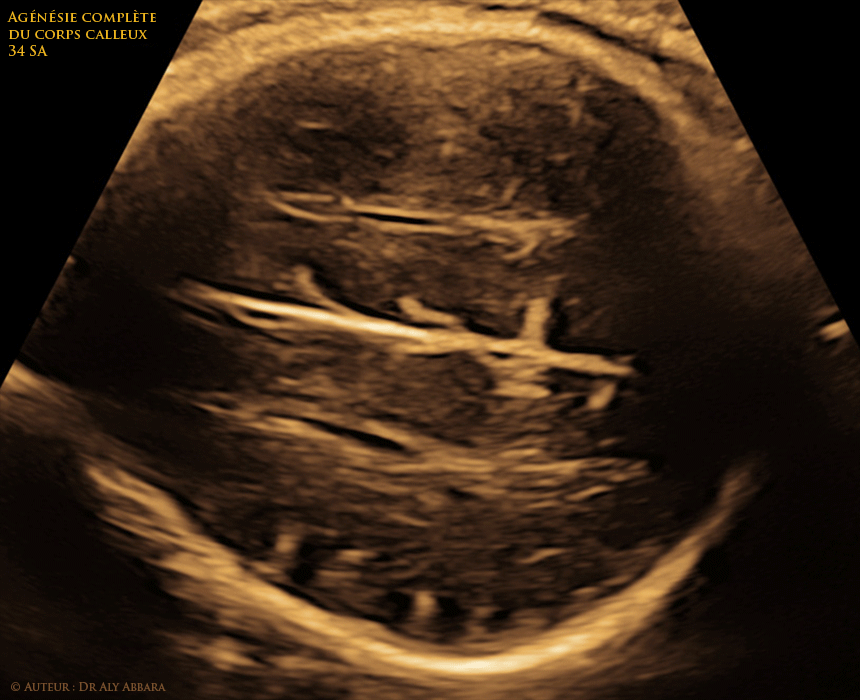

Images et séquences vidéo échographique montrant la présence d'une agénésie complète du corps calleux chez un foetus âgé de 34 SA.

On identifie sur ces images :

• Une dilatation des ventricules latéraux :

• cette dilatation ventriculaire est localisée particulièrement au niveau des cornes postérieures tout en épargnant les cornes antérieures qui conservent leur diamètre normal ; ce phénomène donne aux ventricules latéraux dilatés l'aspect d'une "goutte d'eau" reconnue sous l'appellation " colpocéphalie ".

• l'absence du cavum du septum pellucidum entraînent un écartement excessif entre les cornes antérieures des ventricules latéraux et leur parallélisme l'une par rapport l'autre et par rapport avec la ligne médiane.